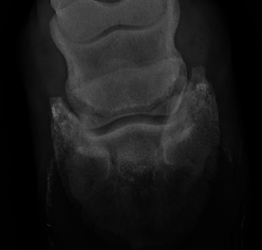

Osteochondritis Dissecans (OCD)